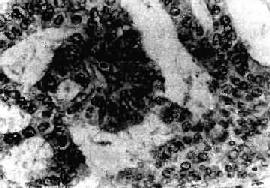

图13-9 子宫内膜腺癌

呈腺样结构,癌细胞呈柱状和立方形,核异型明显,排列紊乱

镜下,子宫内膜癌多数为分化较好的腺癌。腺体数目增多,形状和大小不一,排列紊乱,腺体呈“背靠背”形式。腺体由单层或复层细胞组成,形成条索状“搭桥”。间质极少。有时腺上皮增生形成实体性癌巢。癌细胞呈柱状或多角形,可有不同程度的分化。胞浆中等量,淡染;核大小不一,染色质增多而深染,核仁明显,可有正常或病理核分裂像。根据分化程度,子宫内膜癌可分为3级:Ⅰ级(高分化腺癌),腺体较规则,同单层细胞组成,细胞排列紧密有的成假复层或复层。核分裂像少见(图13-9)。Ⅱ型(中分化腺癌),腺体不规则,有较多腺样结构或小腺体形成,可有少量实性区。癌细胞分化较差,核分裂像易见。Ⅲ级(低分化腺癌),腺体结构极少见,癌巢多呈实性片块状,细胞异型性明显,核分裂像多见。有些腺癌组织中可见良性化生的鳞状上皮团,称腺棘癌(adenoacanthoma)。如果腺癌内混有恶性鳞状上皮,称腺鳞癌(adenosquamous carcinoma),多见于分化较差的腺癌。少数子宫内膜癌含有透明细胞,或含粘液的细胞。有些可形成乳头状子宫内膜癌。